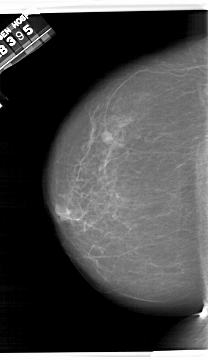

A_1409_1.LEFT_CC

LEFT_CC LINES 6871 PIXELS_PER_LINE 3946 BITS_PER_PIXEL 12 RESOLUTION 43.5 NON_OVERLAY